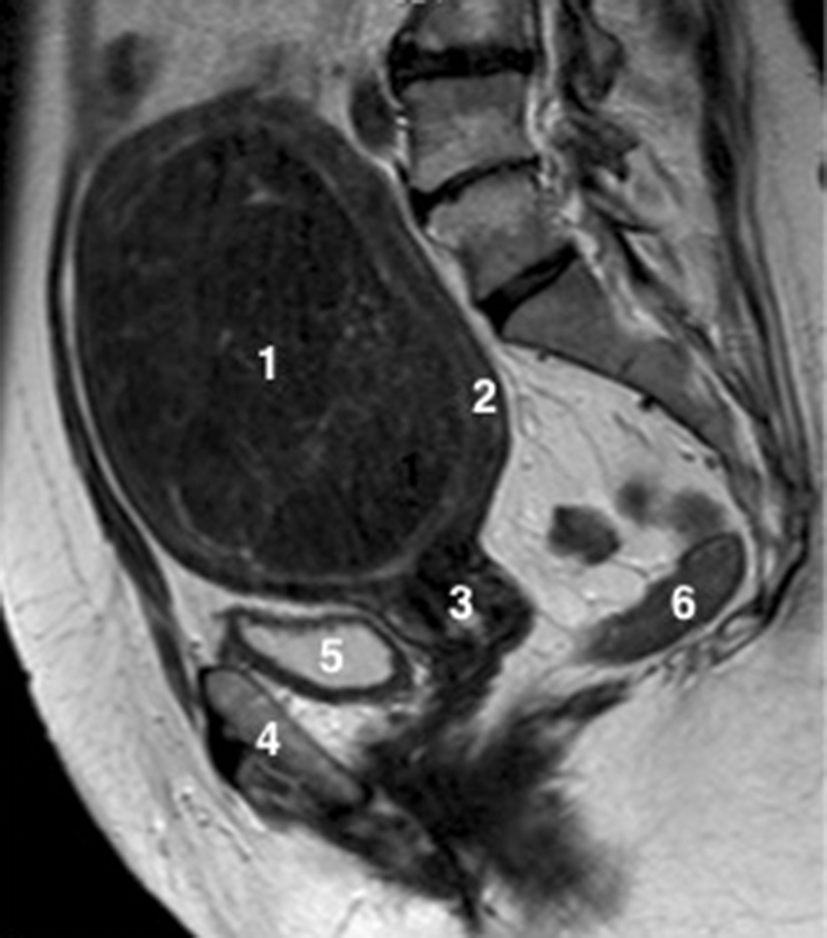

Fig. 20.6 Coupe sagittale d’IRM pelvienne chez une patiente présentant cliniquement une masse pelvienne associée à des ménorragies.

1. Volumineux myome intracavitaire en hyposignal T2, fibreux non suspect. 2. Myomètre refoulé par le myome. 3. Col utérin. 4. Pubis. 5. Vessie. 6. Rectum.

Source : CERF, CNEBMN, 2022.

Fig. 20.7 Coupe coronale d’IRM pelvienne chez une patiente présentant cliniquement une masse pelvienne et des douleurs pelviennes aiguës.

1. Kyste ovarien droit en hypersignal T2 liquidien. 2. Utérus. 3. Trompe droite épaissie et œdématiée, « allongée », en hypersignal T2. 4. Trompe droite de « forme ronde en coupe » témoignant d’un enroulement de celle-ci associé à un épanchement péri-annexiel.